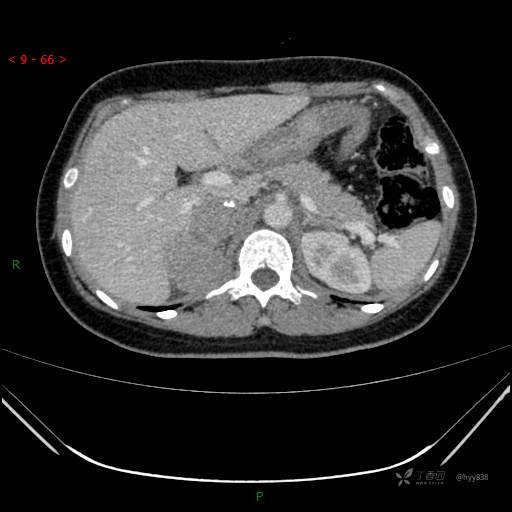

辅助检查:CT

肾上腺CT平扫